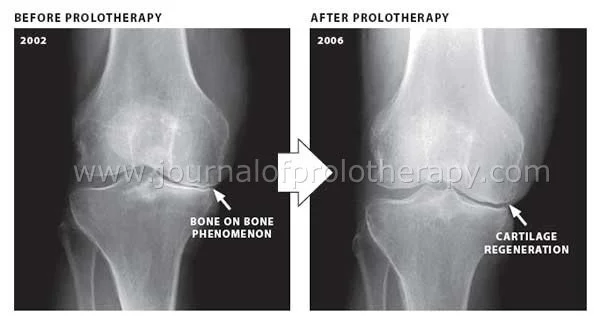

Comparison of knee X-rays showing bone on bone phenomenon in 2002 before prolotheapy and cartilage regeneration in 2006 after prolotheapy.